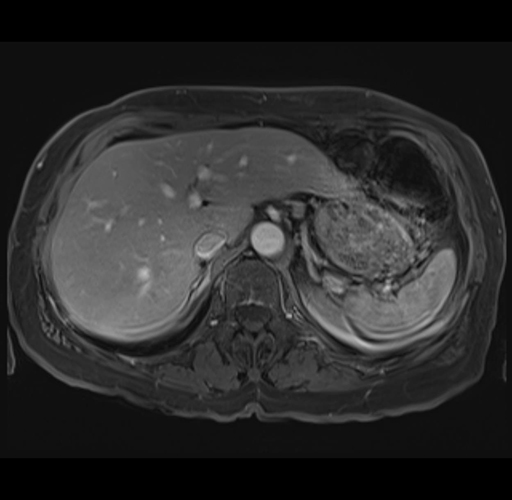

MRI T1